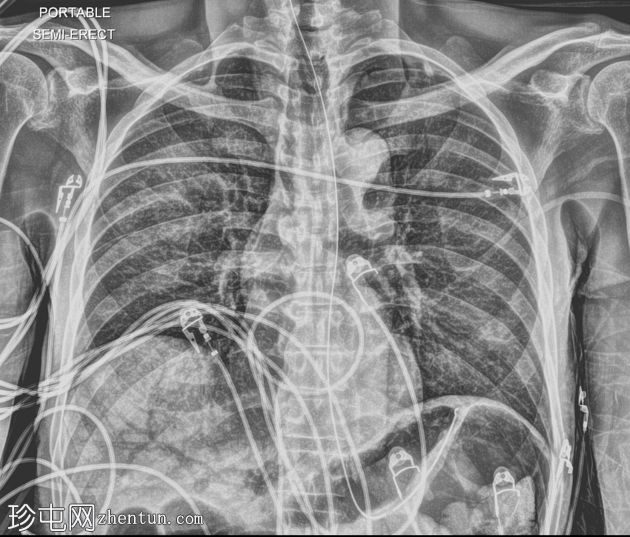

X线片

1.png

正位片